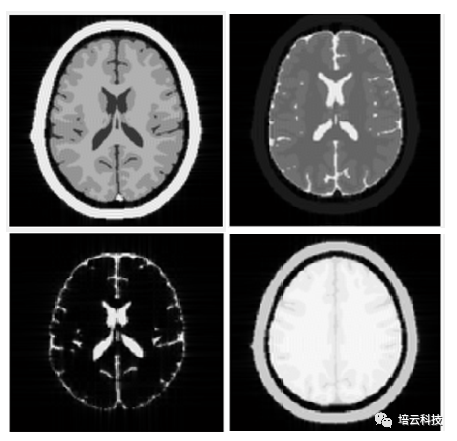

T1权重像上,T1越短的组织越亮,T1越长的组织越暗。脂肪具有短T1,水具有长T1,所以在T1权重像上,脂肪高亮而水体呈现出类似背景的暗黑。T1权重越大,图像信噪比越低。T2权重像上,T2越短的组织越暗,T2越长的组织越亮。脂肪具有中等T2,水具有长T2,所以在T2权重像上,脂肪灰暗而水体高亮。T2权重越大,图像信噪比越低。Pd权重像上,组织的亮度由组织质子密度决定。脂肪和水的质子密度相差不大,很多软组织比如白质和灰质的质子密度和水也差不多。所以质子密度像上,组织的亮度差异很小,但Pd像具有极高的信噪比。综上可知,图像对比度和信噪比也是矛盾的,与信噪比作为矛盾统一体的还有空间分辨率。图10分别是T1WI、T2WI和超重T2权重的水成像以及PdWI的仿真图像效果。水成像上,除了水体是亮的,其余所有组织都是暗的。

图10 T1WI、T2WI和超重T2权重的水成像以及PdWI的仿真图像效果